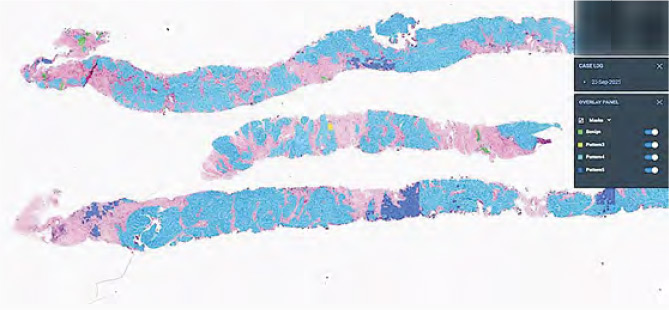

【明報專訊】新一份《施政報告》提出引進數字病理學技術及人工智能(AI)的應用。新界東醫院聯網推行全港首個遙距病理冷凍切片服務,前年起透過將病人樣本轉化成電子圖像等技術,讓北區醫院病理科醫生可遙距為大埔那打素醫院做副甲狀腺切除手術即場冷凍切片診斷,毋須再親身跨院處理,並正計劃擴展手術種類。兩院亦正試行以AI輔助為乳癌及前列腺癌樣本診斷,預計明年2至3月開始正式使用。

有別於以往需跨院到部分手術臨場作冷凍切片診斷,現時大埔那打素醫院駐院醫務化驗師只需在北區醫院病理科醫生遙距支援下做樣本切片,並將樣本數碼化後,北區醫院病理科醫生已可透過樣本影像,遙距為大埔那打素醫院做診斷。

該兩院病理學部門將化驗樣本數字病理化後,亦購入AI軟件,試行以AI輔助為乳癌及前列腺癌診斷,計劃明年2至3月開始使用,用途包括點算乳腺癌細胞,並以AI標示前列腺組織樣本病變情况。